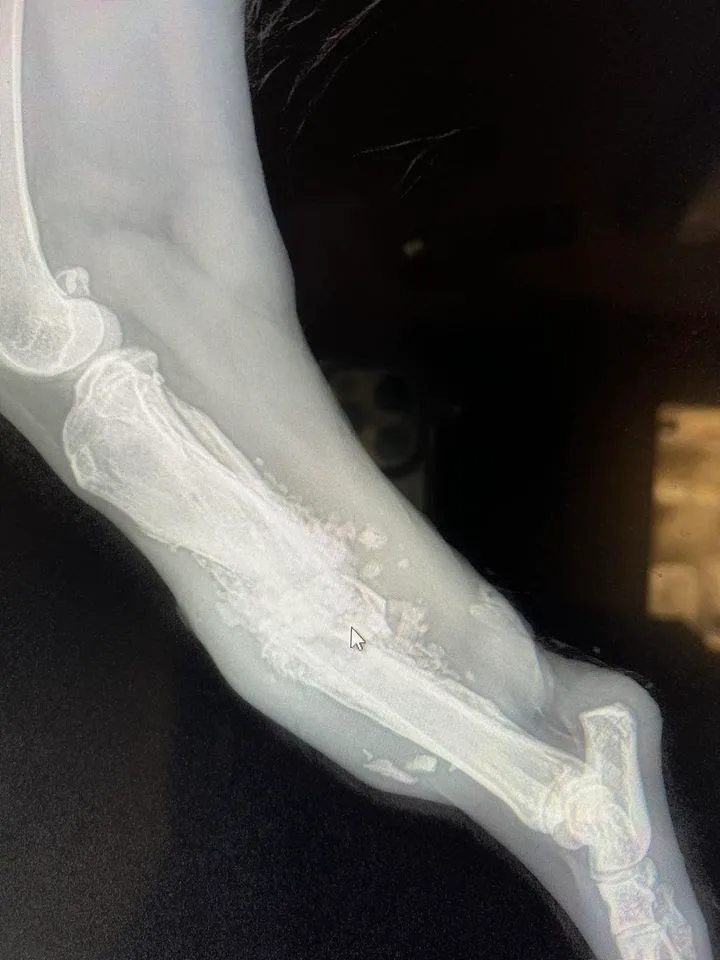

Salvation came for Rocky last week and not a moment too soon. He is emaciated, every bone in his body sharp under nothing but skin. Rocky also had a grievous wound to his rear right leg. It was swollen, badly infected. X-rays revealed it was also shattered. And still, he is pure sweetness and light. He is so happy to have good food, good care, pain medication, antibiotics…but mostly love. He can’t get enough. He revels in it. His smile is a joy to behold. His happiness is contagious.

Due to the extent of damage and infection the only option is to take Rocky’s leg to save his life. Rocky deserves everything good in this world. Everything he was previously denied. We want to be sure he gets the chance to have it. I hope you do too. If you can help with a donation to his surgery, Rocky and I would be so grateful. I’ll update once his surgery is done and he’s out of the hospital. Thank you for your support for deserving dogs like Rocky!